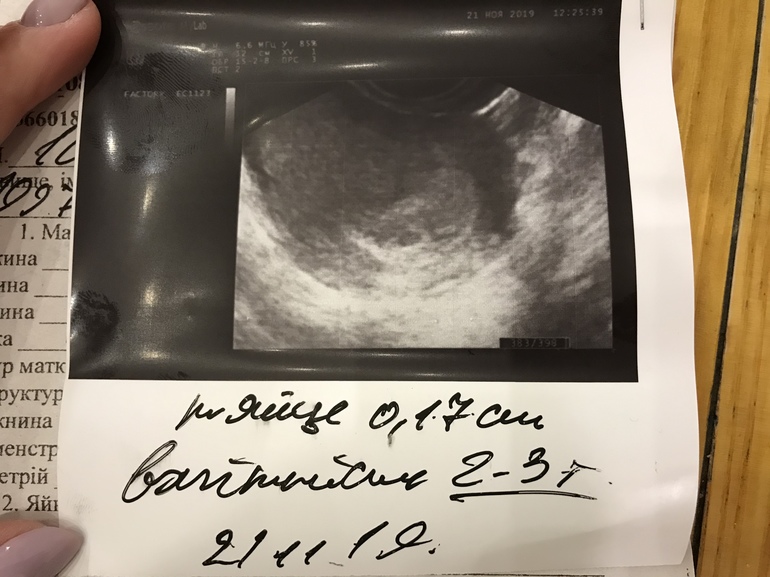

Первое узи

Беременность- 1 триместр ( только до 10 недель)Сегодня пошли на узи подтвердили беременность только с акушерским сроком должно быть 5-6 недель а по узи ПЯ срок 2-3 недели. Если считать от О то получается 3 недели. Но в целом всё хорошо я довольна 😊

Ути Бозе какие крошки 😂 мы до 7 ждём сердечко слушать 😂 с первым ребетенком ещё не знала плодное яйцо 5 мм нашли думала это и есть детёныш 🤣🤣🤣

21.11.2019